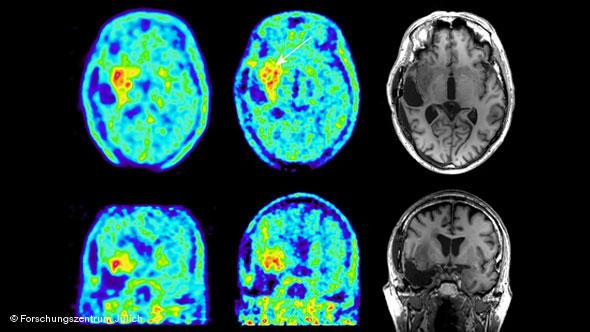

Vaccines to activate the immune system to specifically recognie mutated proteins have reduced and eliminated tumors in mice with human-like immune systems says Dr. Michael Platten of the University of Heidelberg’s brain clinic. The first trial with 29 patients is being carried out this year.